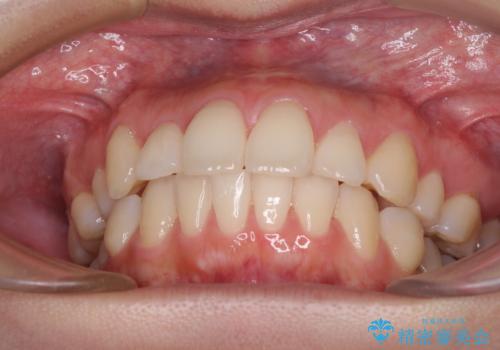

再矯正で突出した口元を引っ込める 抜歯矯正の後戻り

- 抜歯矯正の後戻りで前歯が突出してきていることを気にして来院された患者様です。

口元の突出感を改善するにあたり、抜歯矯正は行うことができないため、奥歯の後方移動とIPR(歯と歯の間を削る)により達成することとしました。

再度後戻りしたときに対応しやすいよう、インビザラインにて矯正治療を行うこととしました。

しっかりと装着時間を守り、ゴムかけにも協力していただいたので、口元を引っ込めることができました。